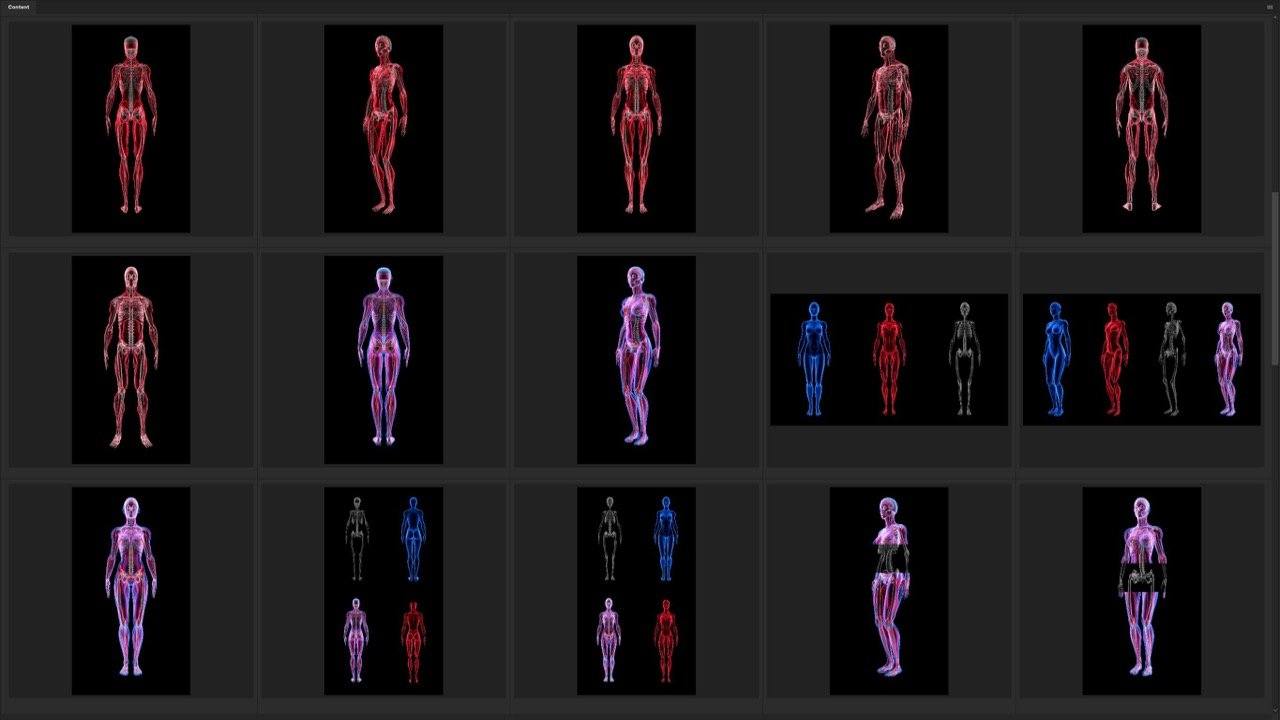

Versatility and Variety

Our Stock-Packs™ are curated to include a varied

range of angles, motion, styles and formats,

ensuring that creators can find the assets

they want fast and easy.